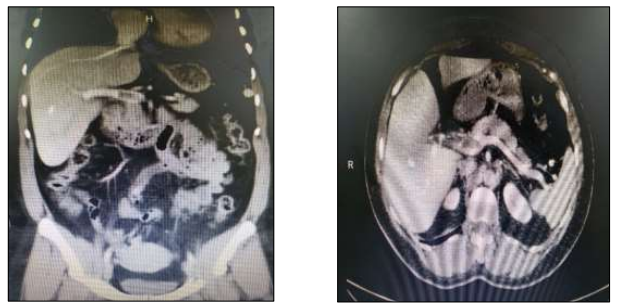

Paciente,sexo feminino, 33 anos, tabagista, apresenta quadro de dor abdominal difusa associada a náuseas e leve distensão abdominal.Nega episódios e cirurgias prévias. Ao exame físico: bom estado geral; hidratada; FC: 85 bpm; PA: 110 x 72 mmHg; FR: 18 irpm; abdômen globoso; RHA+; flácido; e,sem sinais de peritonite; doloroso à palpação profunda de região mesogástrica. Exames laboratoriais sem alterações. Realizada tomografia de abdômen total com contraste:

Além de medidas de suporte, a conduta terapêutica considerada de primeira linha é: